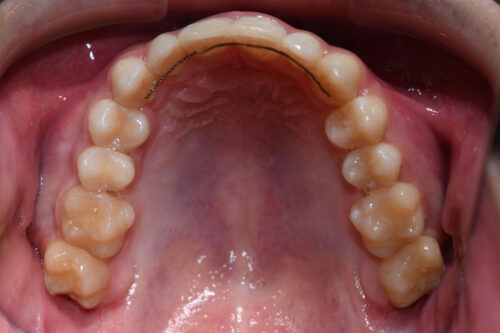

ワイヤー矯正治療 8か月後です。

歯科矯正用アンカースクリュー(デュアル・トップオートスクリュー)上顎左右2本(25000円x2本分 提携医院にて)

ワイヤー期間 7か月,

矯正矯正用アンカースクリュー(デュアル・トップオートスクリュー)上顎左右2本使用することで

下あごの オートローテーションを利用し

歯を抜かない矯正治療でも

口元が出っ歯にならずに

仕上げることができます。